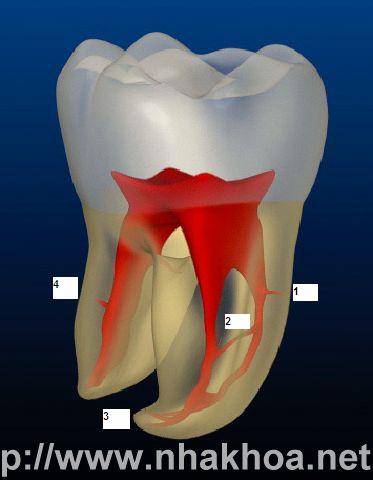

Đây là răng số 6 hàm dưới điển hình của người trưởng thành

Tuỷ răng với các đường tuỷ phụ chia nhánh ngang thân răng ỏ 1, 2, 3, 4